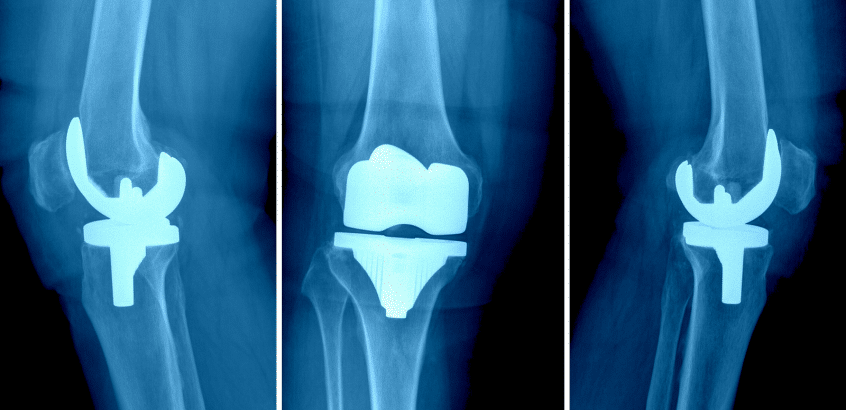

Las infecciones periprotésicas son una de las principales complicaciones en artroplastias totales. De acuerdo con la revista Acta Ortopédica Mexicana, la falla por infección tras una artroplastia total de rodilla presenta una incidencia de entre el 2% y el 4%.

Entre las opciones terapéuticas, la cirugía de revisión en dos etapas es uno de los abordajes utilizados para el tratamiento de infecciones crónicas tras artroplastia total de rodilla. En este contexto, se han estudiado sistemas de liberación local de antibióticos para el control de la infección, como STIMULAN; un biomaterial hecho a base de sulfato de calcio que libera concentraciones de antibióticos en el sitio quirúrgico durante su proceso de reabsorción.

Un estudio retrospectivo evaluó la eficacia y seguridad del uso de sulfato de calcio cargado con antibiótico en cirugías de revisión en dos etapas para infección periprotésica de rodilla, comparando los resultados clínicos de pacientes tratados con este biomaterial frente a un grupo de control emparejado, en el que se realizó únicamente desbridamiento y colocación de espaciadores de cemento con antibióticos.